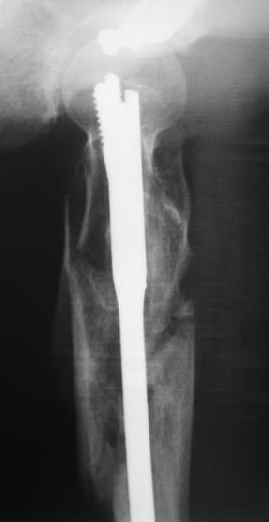

a> Диагноз Закрытый оскольчатый подвертельный перелом правой

a> бедренной кости со смещением отломков,

a> оскольчатый перелом большого вертела, отрывной перелом малого вертела.

Наверно, можно и так сказать, но можно и тоже самое - 4-фрагментный вертельный перелом. Выбор тот же, но с учетом молодого возраста реконструкционный гвоздь тут более применим. Вот уже наш пример.